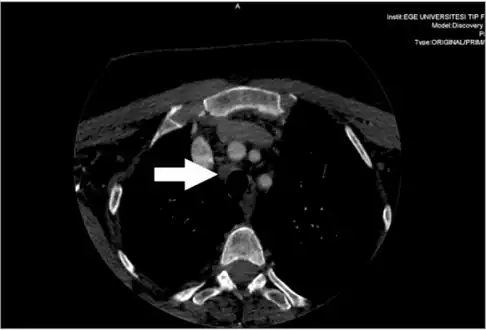

Metastatic central lymph node of a medullary thyroid cancer case

Diagnosis is primarily performed via fine needle aspiration of the lesion of the thyroid to distinguish it from other types of thyroid lesions.[6] Microscopic examination will show an amyloid stroma with hyperplasia of parafollicular cells.